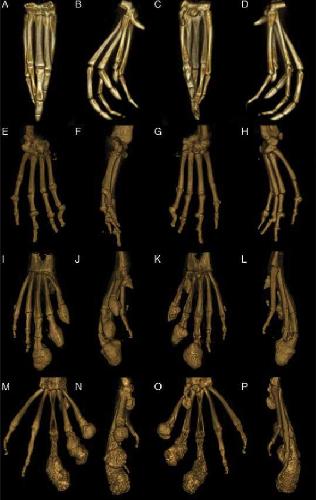

Figure 4. Reconstructed 3D volume renderings of a normal pes (A-D), a severely affected manus (E-H), a severely affected pes (I-L), and the most severely affected pes (M-P). A, E, I and M are dorsal views; B, F, J, and N are medial views, C, G, K, and O are palmar/plantar views, and D, H, L, and P are lateral views. A-D: Normal pes. E-H: Severely affected manus with severe periarticular and articular new bone formation in multi- ple MCP and IP joints with malangulation and subluxation of the IP joint. I-L: Severely affected pes that has rounded peripherally mineralized lesions on digits 0-III which extend proximal to the IP. There is severe linear mineralization plantar to digits I-IV in the flexor tendons. Similar to the manus, there is periarticular and articular new bone formation in the MTP and IP joints in the nonclawed digits and of the clawed digits proximal to the rounded lesions. M-P: Most severely affected pes with rounded peripherally mineralized lesions extending to the proximal phalanx, linear mineralization plantar to digits I-III, and severe periarticular new bone formation.